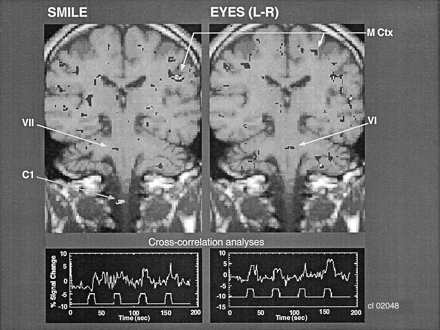

Figure 2 shows a comparison of the regions of BOLD activity in the same individual in the same brain section obtained with two tasks that involve closely adjacent, but different, CN motor nuclei. The task of alternating between smiling and puckering the lips was correlated with BOLD activation in the region of the facial nucleus (CN VII). By contrast, eye movement (ie, shifting the eyes laterally with alternating left-to-right movement) was correlated with BOLD activation in the pons in the region of the abducens nucleus (CN VI), which provides the motor innervation of the lateral rectus muscles of the eye. The abducens nucleus is near the midline, whereas the facial nucleus is lateral to it, at about the same level of the neuraxis. Note that the region of BOLD activation in the cortex corresponded to the homuncular region of the face, consistent with the activation in the brainstem. Also shown in Figure 2 is the cross-correlation time series data. The upper part of each of the traces shows the time course of the BOLD signal change in these ROIs. The lower part shows the time course of the stimulus input; the peak represents the activity of the paradigm, which alternates with the baseline.

Coronal images show that facial and eye movements activate different adjacent brain regions that correspond to the facial and abducens CN nuclei, respectively. Cross-correlation analysis was performed between the onset and termination of the movements and the BOLD signal change in these pontine regions of activation. C1 indicates the C1 level of the spinal cord; M Ctx, motor cortex; VI, CN VI, and VII, CN VII.